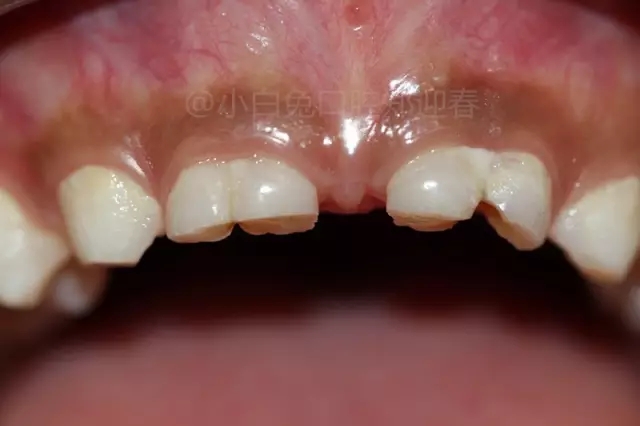

病例分享//一例罕見上頜多牙融合病例

患兒,10歲,因上前牙未替換來診,查體:輕度反合,51和52、61和62均融合,且存在間隙約4mm,全面曲面斷層片顯示:11、21未萌,52、51、61、62牙根均有不同程度的生理性吸收。